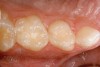

Figure 12  Final view showing treated surface of mesial of tooth A.

Figure 12